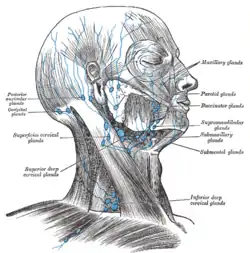

Superficial lymph glands and lymphatic vessels of head and neck (mastoid lymph nodes are labeled as posterior auricular glands at center left) | |

Lymph nodes at surface:

Facial lymph nodes:

The mastoid lymph nodes (retroauricular lymph nodes or posterior auricular glands) are a small group of lymph nodes, usually two in number, located just beneath the ear, on the mastoid insertion of the sternocleidomastoideus muscle, beneath the posterior auricular muscle.

Their mastoid lymph nodes receives lymph from the posterior part of the temporoparietal region, the upper part of the cranial surface of the visible ear and the back of the ear canal. The lymph then passes to the superior deep cervical glands.